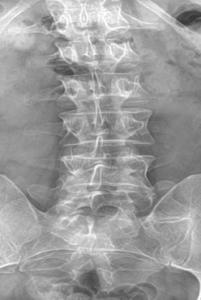

Our patient is a 35-year-old male with low back pain, accompanied by left lower extremity radicular symptoms.

We can see that the L5 vertebral segment is transitional with a broadened left transverse process that forms an anomalous articulation with the sacrum. The right transverse process is normal. The L5/S1 disc does not show signs of degeneration and is generally preserved, but the L4/5 disc level shows early degenerative signs such as spondylophyte formation. As will be discussed in the next section, this is a Castellvi type IIa lumbosacral transitional vertebrae.